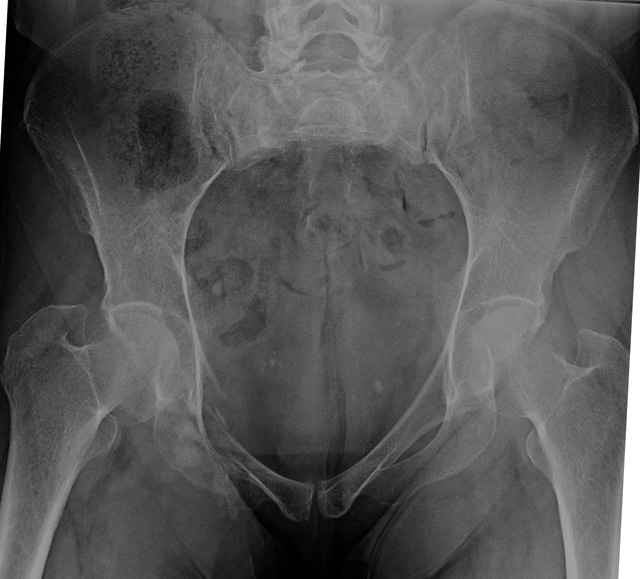

hello everyone, attached are images of a 59 yo female, admitted today after motor vehicle collision. Pt states her pelvis has been very painful ever since she fell on her buttocks from ground level a little over a year ago. medical history significant for scleroderma, raynauds syndrome, and COPD. no past surgeries.

pt states she is very limited in walking ability secondary to pain. she requires a cane or a walker. friends and family do her shopping. the pain is localized primarily around left upper groin. she points to the rami region.

the question is if her medical history is contributing to the nonunions, and if anyone would consider surgical intervention, or is there some other successful intervention?

I’ve operated on 30-35 similar symptomatic patients... usually females in that same age range and most with prior trauma and then with sustained chronic activity related pain due to presumed insufficient healing and resultant ring instability (enough to hurt but not displace too much)...almost all have xray evidence of most of us would consider “hypertrophic” ramus nonunions, and most all have some form of sacral or other posterior ring corresponding injury.

If you examine them for mechanical ring instability, you’ll feel them collapse in your hands as you do... most are overweight to fat to downright obese so the mechanical examination can be a real challenge, but when you anesthetize them you can repeat it under fluoroscopy and see the ramus collapse and displace.